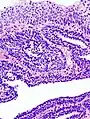

| Micrograph of an inverted papilloma of the urinary bladder. H&E stain. | |

An inverted papilloma, also known as Ringertz tumour,[1] is a type of tumor in which surface epithelial cells grow downward into the underlying supportive tissue. It may occur in the nose and/or sinuses or in the urinary tract (bladder, renal pelvis, ureter, urethra). When it occurs in the nose or sinuses, it may cause symptoms similar to those caused by sinusitis, such as nasal congestion. When it occurs in the urinary tract, it may cause blood in the urine.